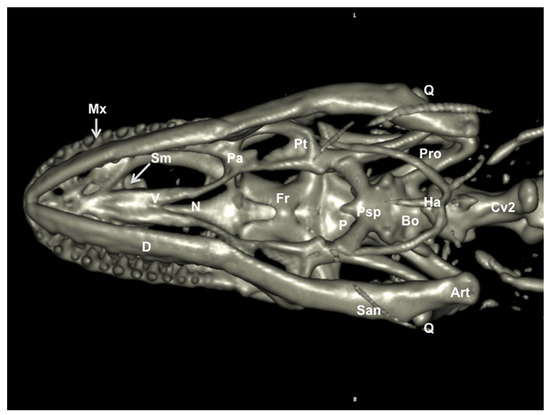

3.2. Head Volume-Rendered Reconstructed Images